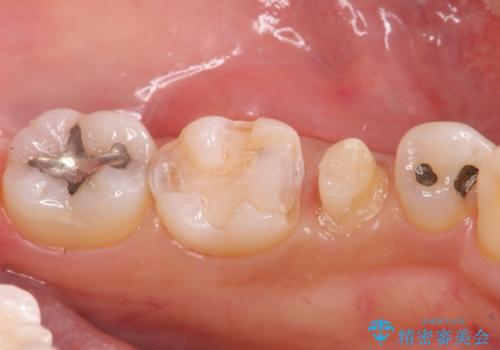

- 左下の奥歯に虫歯がある気がするとのことで来院された患者様です。

手前はジルコニアクラウンで白く、奥はゴールドアンレーでより適合の良いものを装着します。

銀歯の裏側に虫歯が確認されました。

小さな段差も虫歯のリスクにつながります。

精度の良い補綴物を入れることで今後の虫歯リスクを抑えることができます。